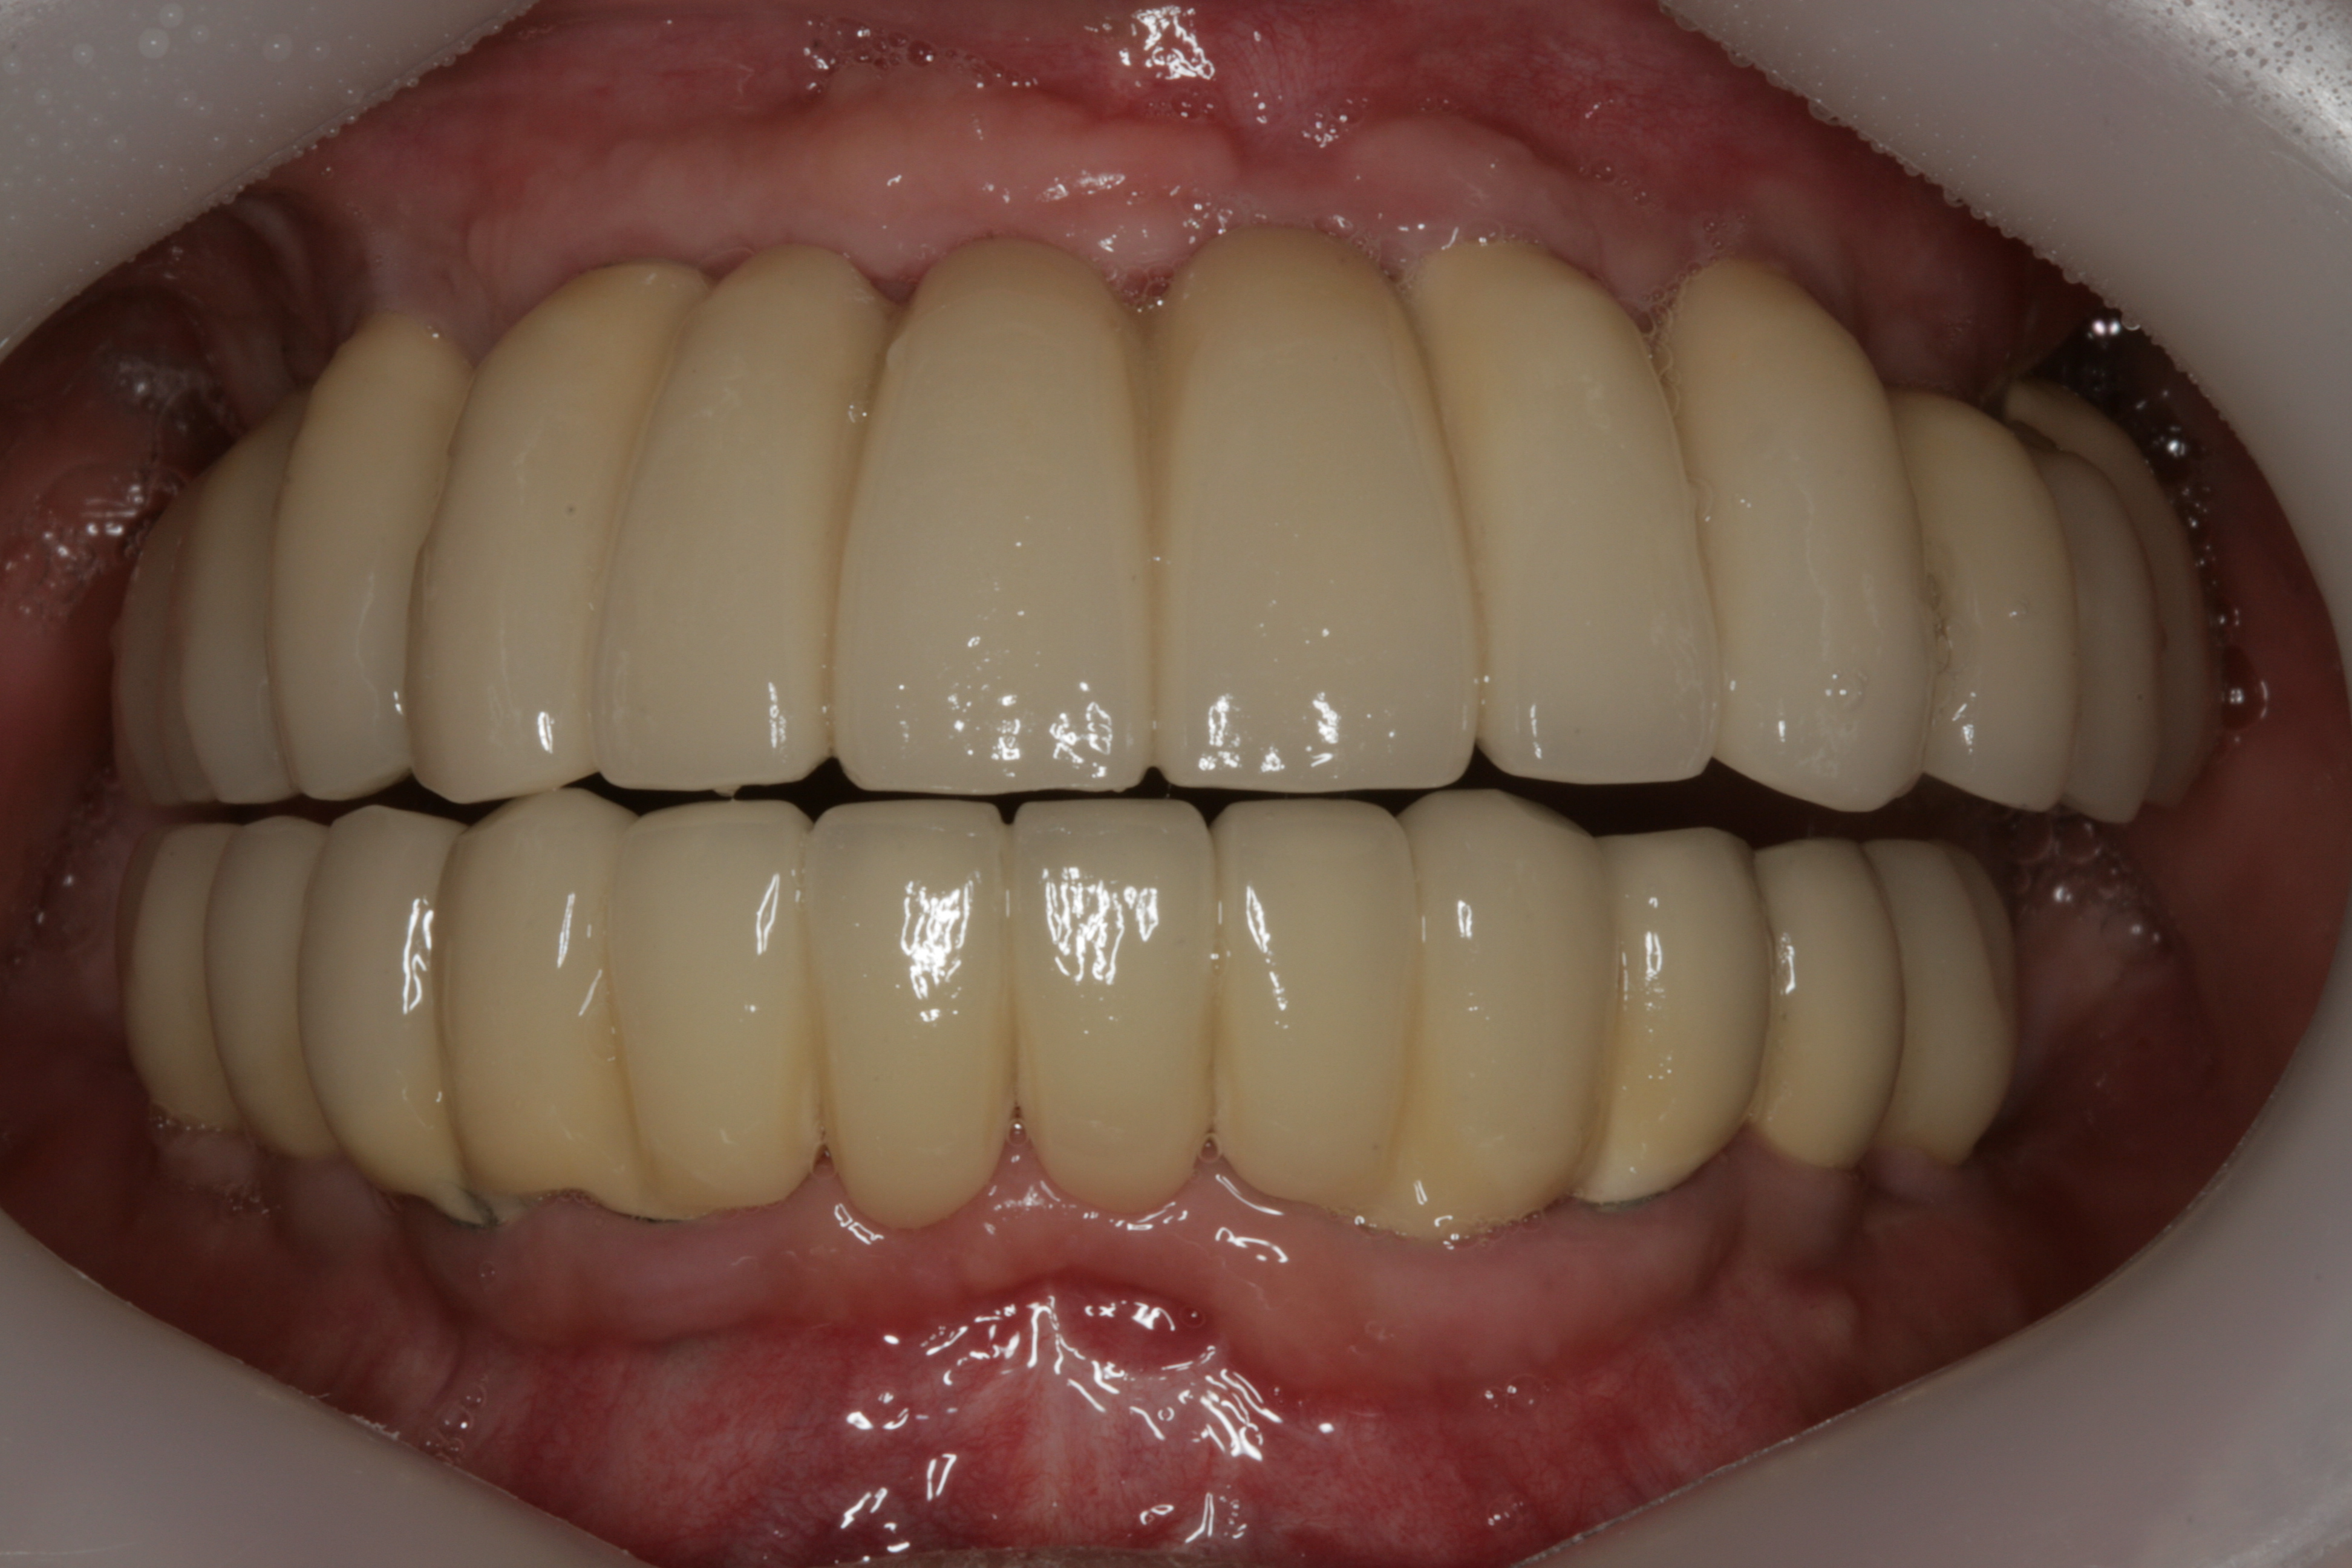

최종 보철물까지 올리고 난 후 구강 내 사진입니다.

평상시의 교합 뿐만아니라 좌우로 아래턱을 크게 움직였을 때도 불편함이 없습니다.